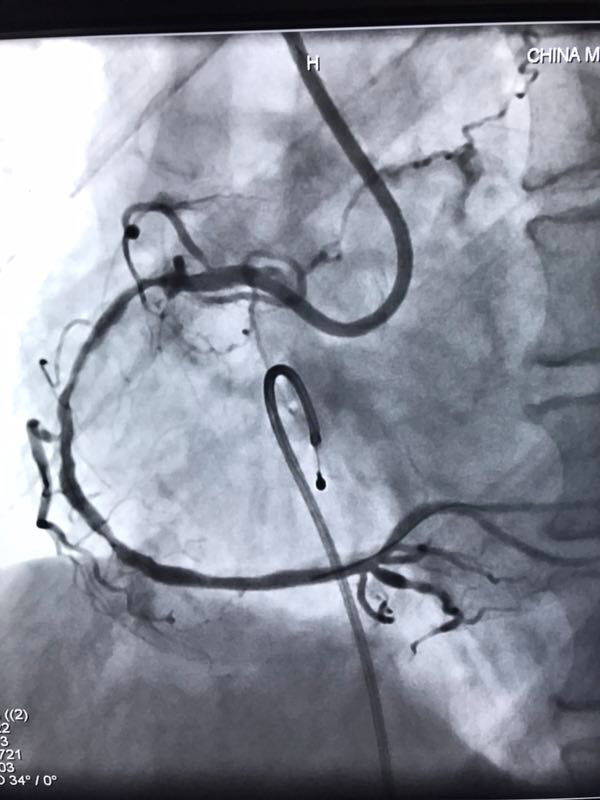

据了解,三位患者都是因严重心绞痛和非ST心梗入院,最高年龄88岁,另两名也有70多岁,是普通PCI难以治疗的危重患者。其中两名已辗转多家医院,均未得到有效救治。患者转入我院后,我院心内科在吴迪主任的带领下,经过周密的准备和科学评估,在血管内超声和临时起搏的辅助指引下,圆满完成了三台旋磨加PCI手术,术后IVUS显示治疗部位支架充分覆盖贴壁,彻底解决了三位患者的病痛,改善了长期预后。

据吴迪主任介绍,冠脉钙化病变和慢性闭塞病变一直是冠心病介入治疗的两大难题,特别是占20%比例的钙化病变,极大的难度风险及高并发症低成功率对心脏介入医生而言是巨大的壁垒和挑战。冠脉旋磨技术作为国家临床二类新技术,就是针对复杂严重钙化病变,通过特制的金刚石探头,在导丝指引氮气加压推进下送入冠脉,借助每秒高达17万转的高速旋转将钙化部位磨平断开,然后借助切割球囊分解斑块,为最终顺利植入支架创造条件。